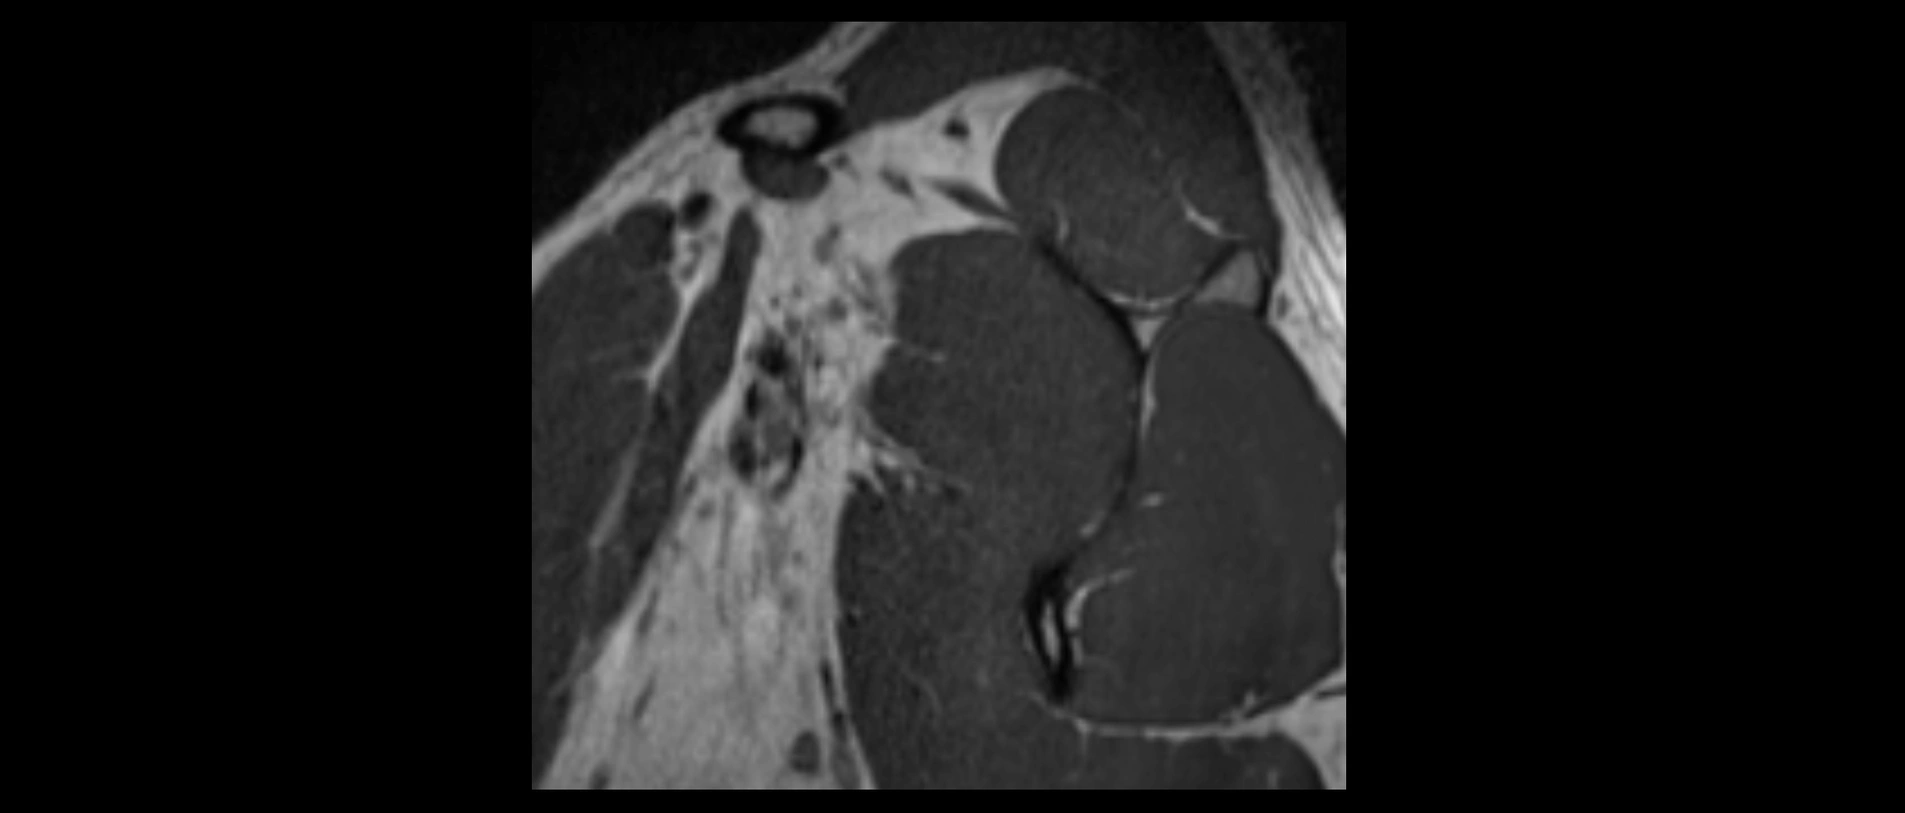

CT image

image

CT Appearance

Non-Contrast CT:

• Ligament: Not directly visualized due to small size and low density.

• Bony landmarks: Lateral clavicle and acromion clearly seen; cortical margins well defined.

• Pathology: Detects fractures, joint subluxation, osteophytes, and degenerative changes.

• Alignment assessment: Evaluates AC joint spacing and clavicular displacement.